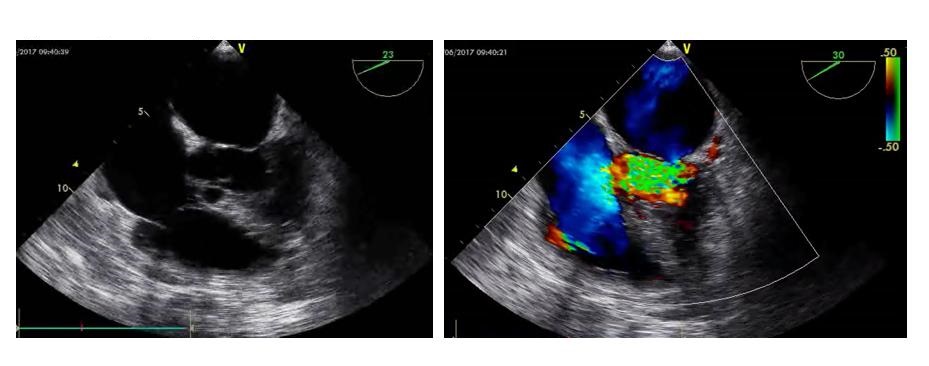

D、瓣膜通过观察瓣膜开合节律和频率评估瓣膜功能及心律失常,二尖瓣开放程度(EPSS)协助评估左心室收缩功能。瓣膜区彩色多普勒超声可评估瓣膜反流、狭窄情况。重度主动脉瓣反流如不能短期内进行外科干预者影响VA-ECMO实施效果(图 6右)。室壁无增厚的右室扩张合并急性三尖瓣、肺动脉瓣反流提示可能存在肺动脉栓塞。呼吸衰竭肺水肿者检查有无二尖瓣脱垂(图 6左)、重度二尖瓣反流。不管是原发还是继发严重瓣膜问题,均可能会在ECMO实施时影响支持效率,因此,建议在ECMO准备阶段筛查瓣膜功能。

| 图 6 可能影响ECMO效果的瓣膜病变 |

5 特殊超声检查和技术 5.1 超声造影超声造影常用于创伤出血患者的脏器破裂、出血部位查找,也常用于心腔内膜的清晰显示。虽然目前在ECMO患者中使用超声造影剂的安全性没有足够证据支持,但已有少量病例报道应用超声造影协助发生南北综合征的VA-ECMO患者寻找血流接触平面位置、判断主动脉瓣反流、协助明确左心室血栓形成(图 29)及撤机后使用超声造影协助评估穿刺点部位血管并发症等多方面应用[25-28]。